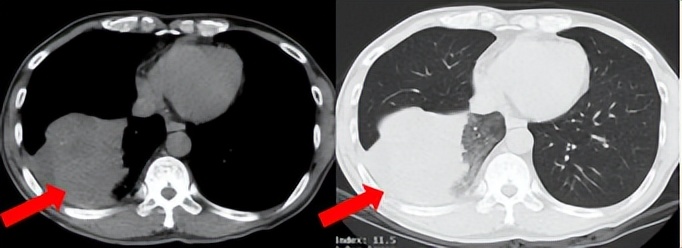

53岁男性,无吸烟饮酒史,脑血栓病史。2024年7月胸部CT:右肺下叶见一团块状软组织密度影,范围约10.8×9.0cm,边界不清,周围并见斑片状磨玻璃密度影,右肺下叶前底段支气管阻塞。纵隔及右肺门见肿大淋巴结影。考虑右肺下叶支气管肺癌。伴纵隔及右肺门淋巴结转移瘤,右下肺静脉瘤栓。2024.7.23行肺穿刺取病理:(肺)腺癌伴有神经内分泌分化。NGS基因检测:RET KIF5B exon15-RET exon12融合。PD-L1(克隆号28-8)TPS=90%。

临床诊断:右肺下叶恶性肿瘤cT4N2aM1a IVA期,肺门淋巴结继发恶性肿瘤,纵隔淋巴结继发恶性肿瘤,胸腔积液,大脑中动脉取栓术后。

治疗经过:2024.08开始口服赛普替尼(160mg,bid)。2024.09复查胸CT评效PR。2025.1复查胸CT:右肺下叶外基底段见一不规则形实性肿块,大小约94mm×87mm,边缘呈分叶状,其内密度不匀。右侧胸腔见少许水样密度影。评效PD,PFS=5个月。患者未同意再次组织活检,目前应用卡博替尼治疗,仍在随访中。治疗期间未出现毒性反应。

2024.08

2024.09评效PR

2025.01评效PD